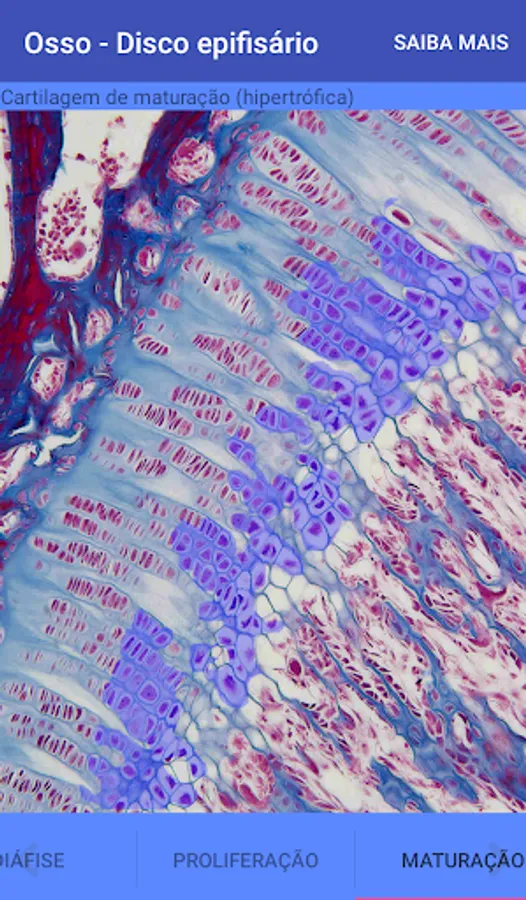

Bone by descaling (Epiphyseal Disc)